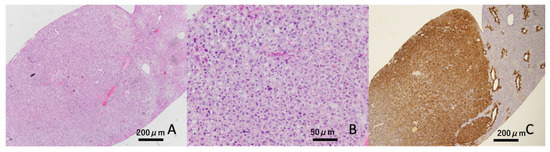

3.6. Histopathological Findings in the Liver